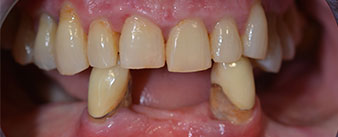

La paciente de 64 años se presentó con una dentición residual compuesta por las piezas dentales 38, 33 y 43 en el maxilar inferior y con una prótesis temporal fijada con ganchos en el maxilar inferior (figs. 1 y 2).

El tratamiento periodóntico necesario y la extracción de las piezas en el maxilar superior debía realizarse en un momento posterior, ya que la paciente es profesora y, en el momento de la consulta, estaba ocupada con los exámenes para las pruebas de acceso a la universidad. La paciente no podía comer ni hablar adecuadamente, ya que la prótesis temporal se rompía con mucha frecuencia y con una carga mínima.